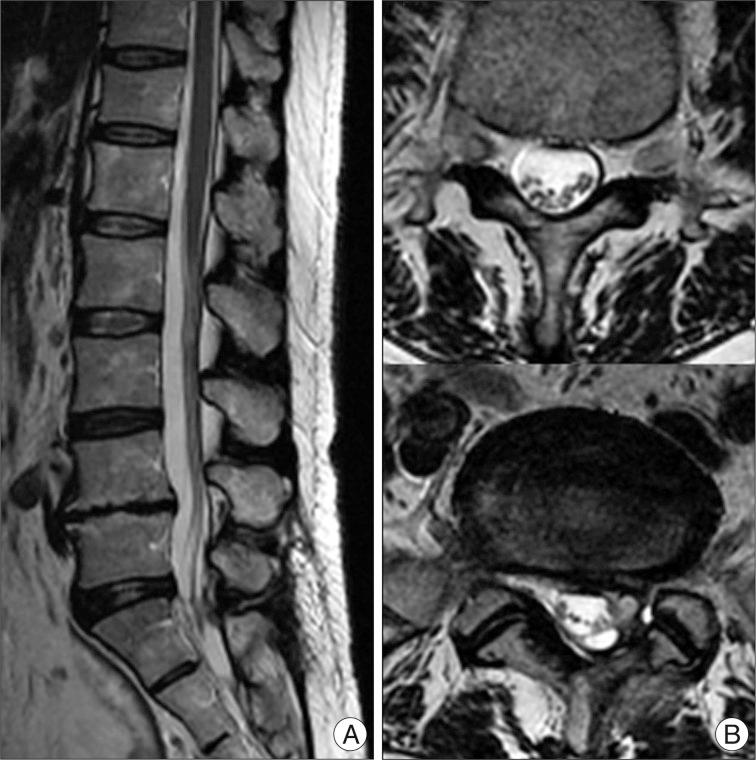

We report a rare complication of iatrogenic spinal intradural following minimally invasive extradural endoscopic procedues in the lumbo-sacral spines. To our knowledge, intradural cyst following epiduroscopy has not been reported in the literature. A 65-year-old woman with back pain related with previous lumbar disc surgery underwent endoscopic epidural neuroplasty and nerve block, but her back pain much aggravated after this procedure. Postoperative magnetic resonance imaging revealed a large intradural cyst from S1-2 to L2-3 displacing the nerve roots anteriorly. On T1 and T2-weighted image, the signal within the cyst had the same intensity as cerebrospinal fluid. The patient underwent partial laminectomy of L5 and intradural exploration, and fenestration of the cystic wall was accomplished. During operation, the communication between the cyst and subarachnoid space was not identified, and the content of the cyst was the same as that of cerebrospinal fluid. Postoperatively, the pain attenuated immediately. Incidental durotomy which occurred during advancing the endoscope through epidural space may be the cause of formation of the intradural cyst. Intrdural cyst should be considered, if a patient complains of new symptoms such as aggravation of back pain after epiduroscopy. Surgical treatment, simple fenestration of the cyst may lead to improved outcome. All the procedures using epiduroscopy should be performed with caution.

我们报告了一例腰骶部微创硬膜外内镜手术后罕见的医源性脊髓硬膜内并发症。据我们所知,文献中尚未报道过硬膜外镜检查后出现硬膜内囊肿的情况。一名65岁女性,因既往腰椎间盘手术相关的背痛接受了内镜下硬膜外神经成形术和神经阻滞,但术后背痛明显加重。术后磁共振成像显示,从S1-2至L2-3有一个巨大的硬膜内囊肿,将神经根向前推移。在T1加权和T2加权图像上,囊肿内信号强度与脑脊液相同。患者接受了L5部分椎板切除术及硬膜内探查,并完成了囊肿壁开窗。手术过程中,未发现囊肿与蛛网膜下腔之间的交通,囊肿内容物与脑脊液相同。术后,疼痛立即减轻。在内镜经硬膜外间隙推进过程中发生的意外硬膜切开可能是硬膜内囊肿形成的原因。如果患者在硬膜外镜检查后出现如背痛加重等新症状,应考虑硬膜内囊肿。手术治疗,单纯囊肿开窗可能会改善预后。所有使用硬膜外镜的操作都应谨慎进行。